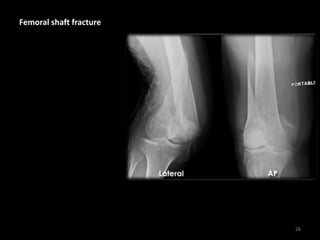

Femoral shaft fracture

26

• Spiral fracture with

posterior angulation,

lateral displacement

and shortening

• There is rotation of the

distal femur so the

knee faces laterally

• X-rays of the proximal

femur (not shown) did

not reveal further

injury

• Injury occurred in a

road traffic crash

27